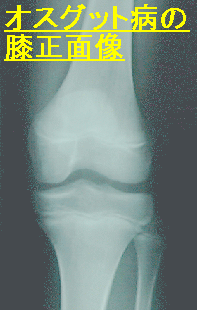

オスグット病